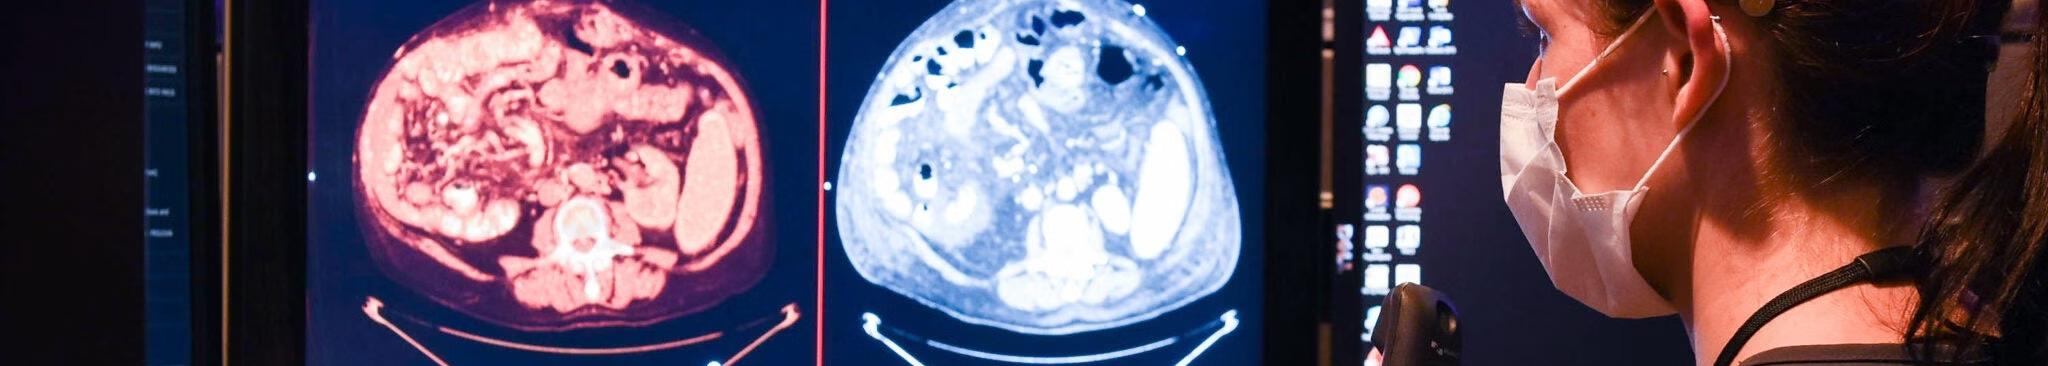

Comprehensive guide to FRCR 2A exam success. by frcr revision

For radiologists

Assess knowledge and skills

In different areas of radiology